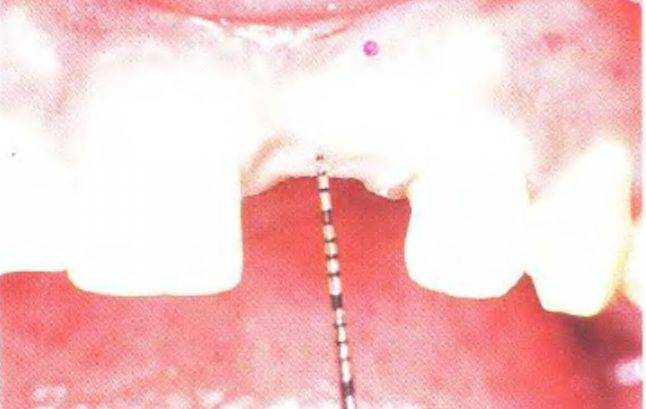

Правильное проведение лучевой диагностики позволяет получить объективную информацию о высоте и толщине кости в области предполагаемой имплантации. Для оценки контуров кости можно измерить толщину десны в проекции ложа имплантата в пяти точках: по центру альвеолярного гребня; в двух точках с вестибулярной стороны; в двух точках с оральной стороны. Измерение проводят под местной анестезией с помощью зондирования стерильной иглой с силиконовым ограничителем и линейки (рис. 3-391 и 3-39т).

То же самое можно проделать с помощью остроконечного пародонтологического зонда с миллимет-

ровой калибровкой (рис. с 3-39п по 3-39г). Полученные данные отметили на спиле модели в проекции предполагаемой имплантации. Такой прием позволяет не только определить оптимальное положение имплантата, но и подобрать абатмент (рис. 3-39s и 3-39t).